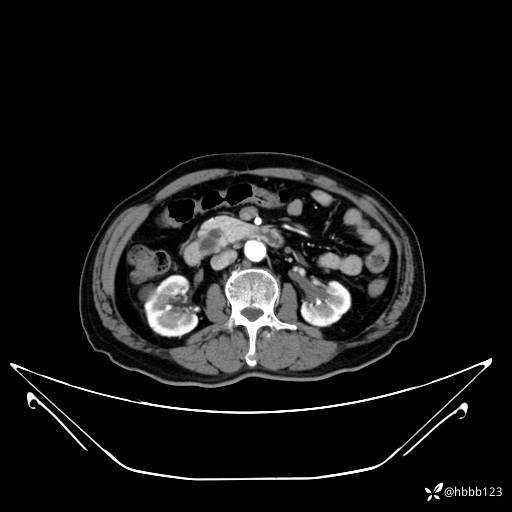

门脉期: